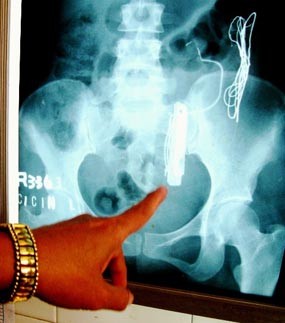

Informasi yang dihimpun dari tim medis yang merawat bahwa perut Cicin ditemukan sejumlah benda sejenis logam. Parahnya, logam itu berupa benda keras semacam silet, tusuk konde, biji streples, kawat dan jepit rambut.

Semua barang logam yang bersarang di tubuh Cicin terungkap, setelah tim medis melakukan foto rontgen perutnya. "Ini pertama kali kami menangani pasien yang perutnya mengandung logam," terang spesialis penyakit dalam yang menangani Cicin, dr Setijohadi, Jumat (28/8/2009).

Setelah dilakukan rontgen, ditemukan beberaap benda logam di perut. Lalu 27 Agustus lalu, dokter kembali melakukan rontgen dan hasilnya sangat mengejutkan, ternyata silet dan jepit rambut telah hilang. Namun logam sejenis kawat dan biji streples masih tampak terlihat.